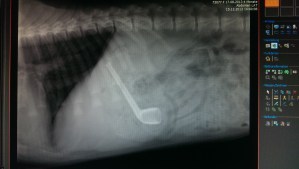

Fressmaschinchen Veröffentlicht am 1. März 2015 von cwaldmann Ein Bild sagt mehr als tausend Worte. Hier habe ich ein besonders schönes, das nach dem Verzehr eines GANZEN Weckmanns erstellt wurde: Dem Labrador ging es nach dem Erbrechen der Weckmann-Pfeife wieder gut… In diesem Sinne: Ihre Tierarztfrau Gefällt mir Wird geladen … Ähnliche Beiträge